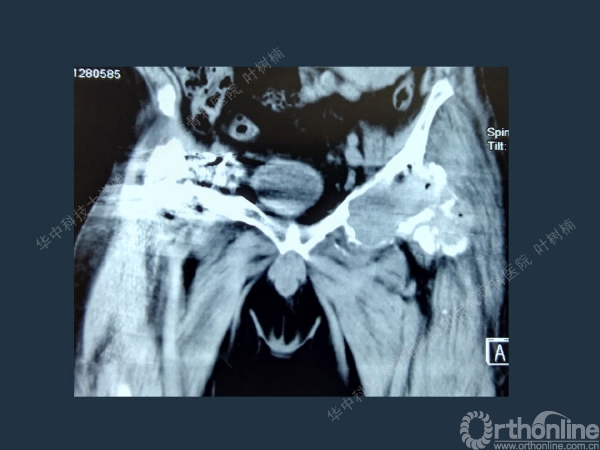

股骨侧翻修

髋臼缺损的处理